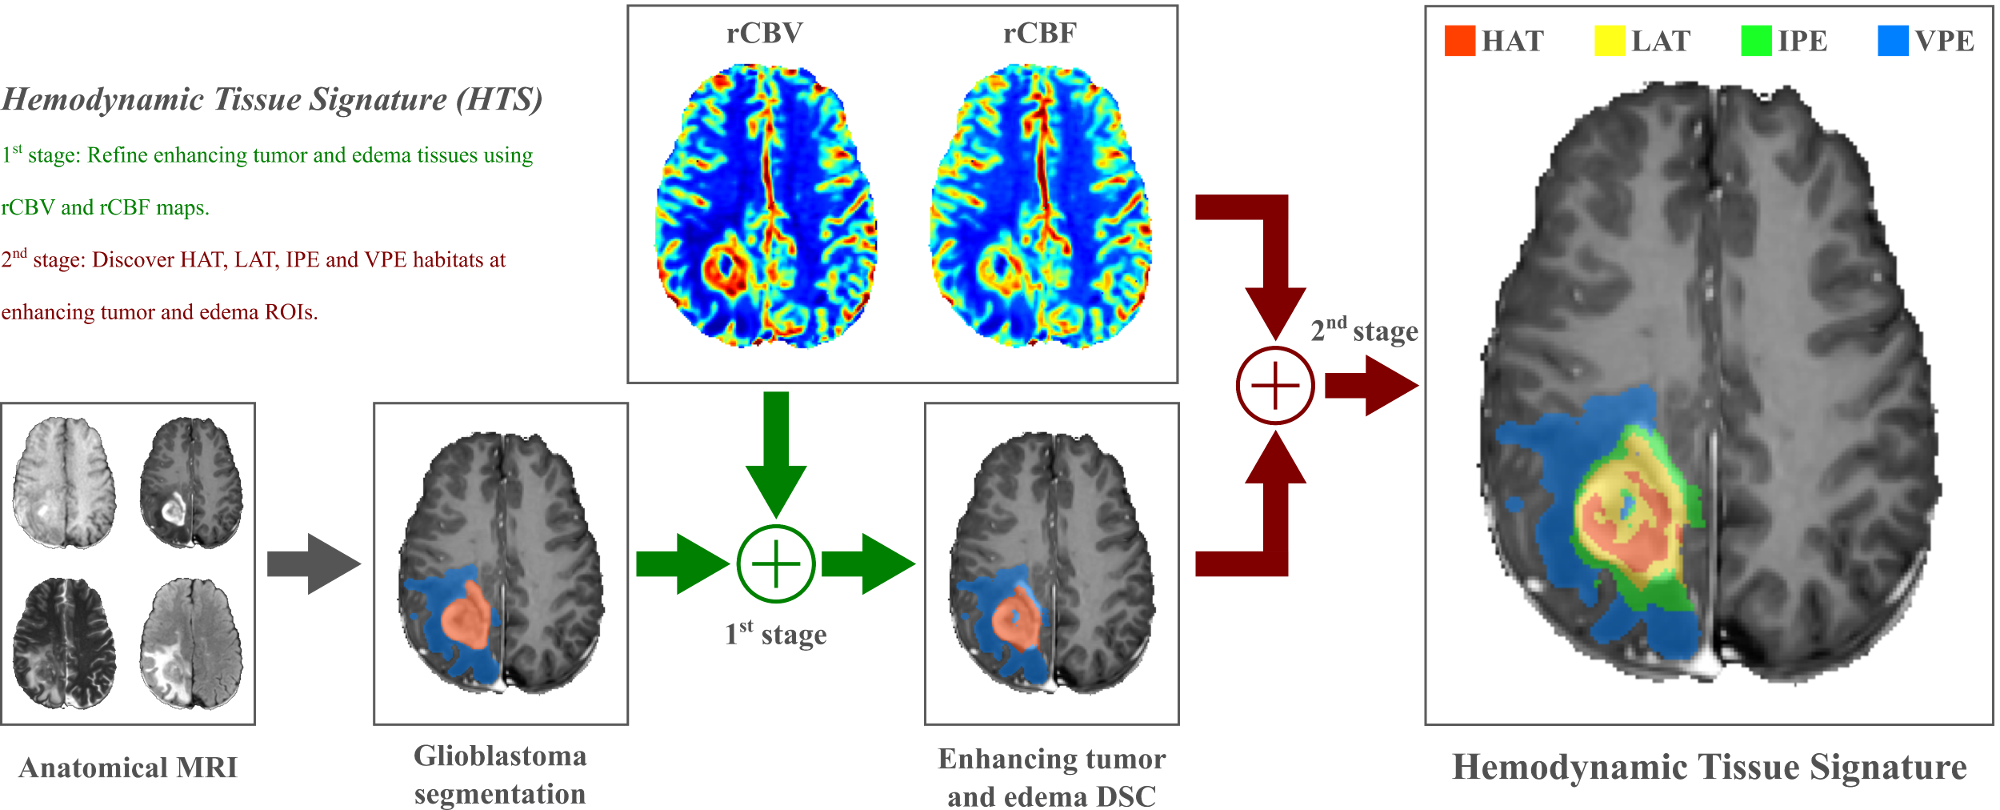

This thesis focuses on the research and development of the Hemodynamic Tissue Signature (HTS) method: an unsupervised ML approach to describe the vascular heterogeneity of glioblastomas by means of perfusion MRI analysis. The HTS builds on the concept of habitats. A habitat is defined as a sub-region of the lesion with a particular MRI profile describing a specific physiological behavior. The HTS method delineates four habitats within the glioblastoma: the High Angiogenic Tumor (HAT) habitat, as the most perfused region of the enhancing tumor; the Low Angiogenic Tumor (LAT) habitat, as the region of the enhancing tumor with a lower angiogenic profile; the potentially Infiltrated Peripheral Edema (IPE) habitat, as the non-enhancing region adjacent to the tumor with elevated perfusion indexes; and the Vasogenic Peripheral Edema (VPE) habitat, as the remaining edema of the lesion with the lowest perfusion profile. The research and development of the HTS method has generated a number of contributions to this thesis.

A method for the vascular heterogeneity assessment of glioblastoma

The Hemodynamic Tissue Signature (HTS) method analyzes the perfusion MRI of a glioblastoma using an unsupervised learning approach to delineate four habitats within the lesion that exhibit different hemodynamic activity. The habitats describe the High Angiogenic Tumor (HAT) and Low Angiogenic Tumor (LAT) regions of the glioblastoma, and the potentially Infiltrated Peripheral Edema (IPE) and Vasogenic Peripheral Edema (VPE) of the lesion. Such approximation establishes a conceptual frame for the description of the tumor heterogeneity by means of the detection of clinically relevant sub-regions, a.k.a habitats, with differentiated imaging biomarkers. The preliminar results of this work were first presented in the conference contribution P4 (Juan-Albarracín et al, 2016) and it was finally published in the journal contribution P5 (Juan-Albarracín et al, 2018).